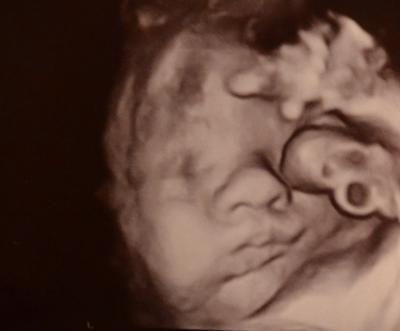

So, ihr Lieben, auch ich hatte gestern mal wieder einen VU-Termin! Alles war super: CTG unauffällig, MuMu zu, Gebärmutterhals 4cm! Unser Pummepprinz ist ca. 45cm groß und soll so um die 1900gr wiegen.......nachdem er ja bis jetzt immer zwei Wochen zu groß war, hat er sich jetzt von der Entwicklung her normalisiert...sagt auf jeden Fall der Arzt! Wirklich wissen werden wir es wohl erst, wenn er da ist! ......und ein Bildchen haben wir auch wieder bekommen! Ich bin ja sooooooo verliebt..... ....dieses Mündchen!!!! .....und diese Stupsnase!!......hach nääääääää!....ich könnte auf der Stelle zerfließen!

Bild zu Gestern beim FA! ;) - Forum für Juni - Mamis